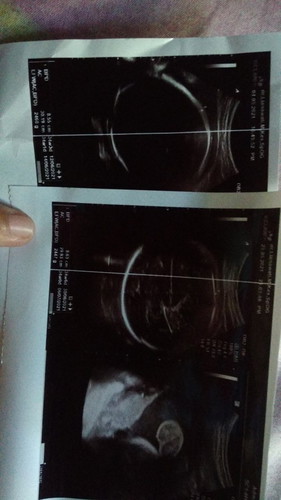

Ibu2, apaakh ada yg pernah mengalami hal yg sama dgn sy? Wsktu tgl 4 bulan ini sy USG dan berat janin sy 2460 gram, dan tadi malam tgl 25 sy USG lagi tp berat bayiku malah menurun jadi 2447 gram. Bukankah sehwrusnya semakin mendekati lahiran maka berat janin akan cepat besar. Ohh yaa usia kandungan saya susah 37 minggu 6 hari. Tp kata dokter aman2 sj, dan debay jg gerak2nya Alhamdulillah masih aktif tp ttp saja sy sedikit worry. Ada yg punya pengalaman seperti sy? #seriusnanya